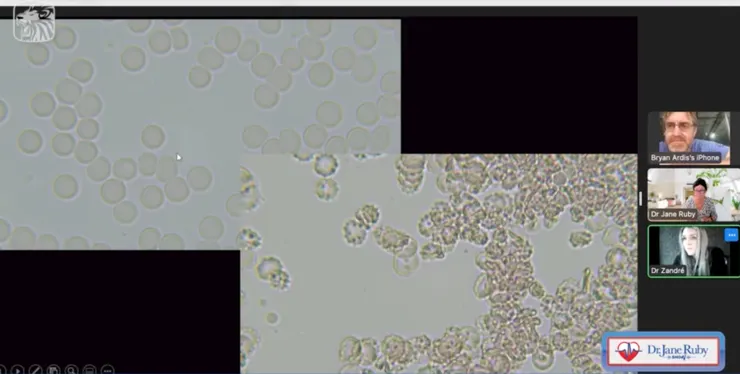

上圖中, 左為Barthe醫師健康血液,右側為滴一滴Pfizer之後...五分鐘之內血球不正常變性,出現鋸齒形紅血球/棘狀細胞。只需一滴.....